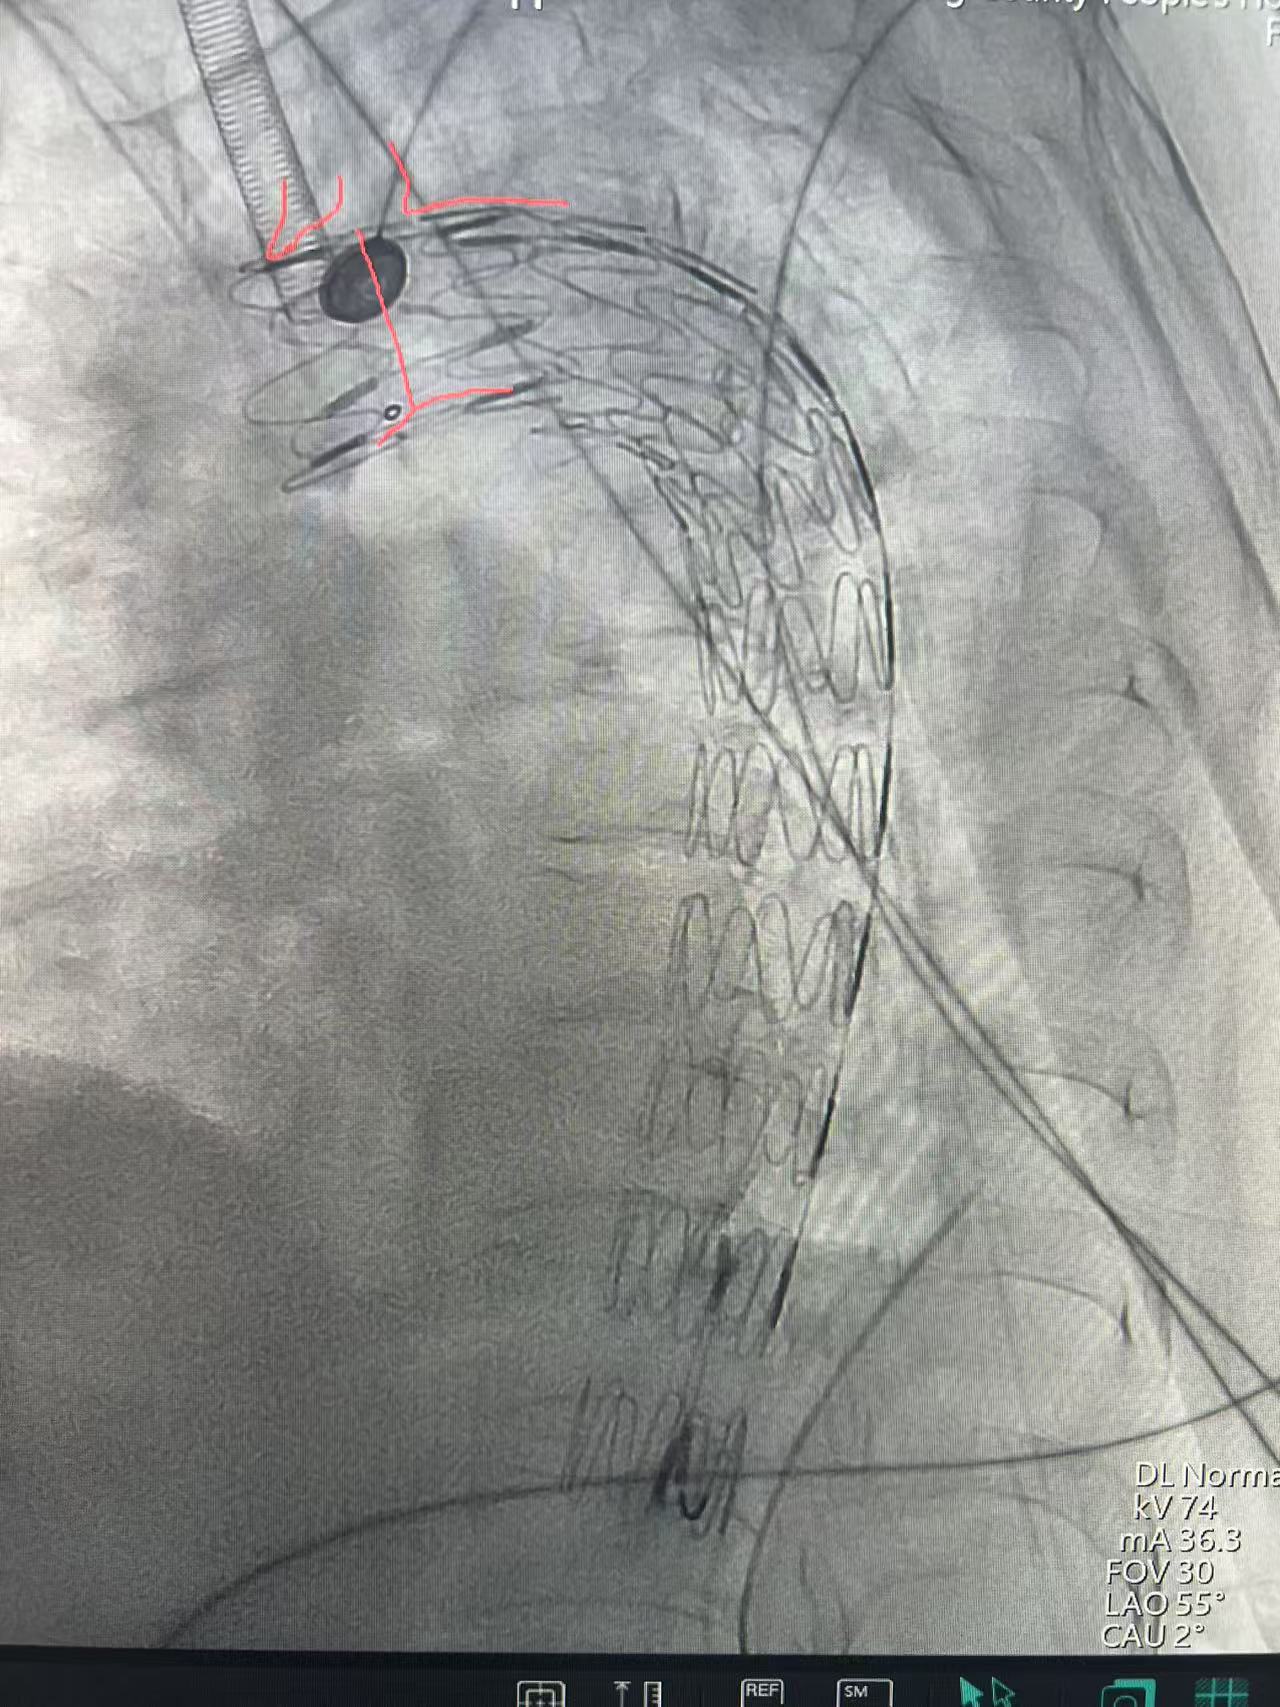

术前

术后

医院重症医学科、胸外科、骨科、医学影像科、麻醉科、介入科等多学科会诊讨论,针对伤情制定合理的治疗方案,在一系列稳定患者血流动力学治疗后,医务科再次针对胸主动脉假性动脉瘤组织多学科会诊。在院外专家指导下为患者实施胸主动脉覆膜支架腔内隔绝的介入手术,手术在数字减影血管造影(DSA)设备的精准引导下,通过患者两侧大腿根部穿刺股动脉,将覆膜支架经血管输送至胸主动脉损伤部位,成功隔绝血管破裂口,有效阻止了破口进一步撕裂。整个手术过程紧张有序,仅耗时40分钟便顺利完成,术中患者生命体征平稳,术后被安全送回重症病房观察。